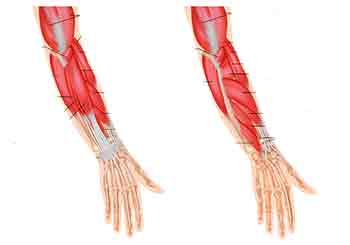

Problems involving the wrist and hand are increasingly common. They are often due to a fall or fracture and also due to repetitive strain syndromes. Sometimes they involve an arthritic pathology. Mostly they are amenable to mobilization of the joints and stretching of the tendons and muscles of the wrist and hand. I have special expertise in this area having treated many classical musicians for example.

Look at the incredible array of muscles in your forearm. I still marvel at the complexity which enables us to perform so many functions with our hands.

I had a case a month ago of a young guitarist who could no longer use his left little finger properly. I attended to the muscles and tendons which control that finger and improvement followed immediately. With computer workers I will examine their workstation set up and habits especially of mouse usage. This approach combined with my specialized techniques all to often bring about a rapid improvement.

These conditions are usually described as above but are usually due to the attachment of the tendons where they meet the elbow. They will radiate pain all around one side or the other. This common condition does not involve inflammation or swelling of the elbow joint and is amenable to mobilization techniques combined with softening of the attachments. Pain can also extend along the forearm.

We can all experience nerve related symptoms. Ranging from pins and needles, numbness and partial paralysis of muscles and limbs. Most of these common symptoms can be relieved by the correct diagnosis and treatment. The more serious central nervous system conditions are more problematic but can still be greatly helped especially with their secondary symptoms such as weakness, loss of co-ordination and worse. The most common nerve related symptom is pins and needles in the hand. This may be due to a number factors and is often mis-diagnosed as carpal tunnel syndrome.